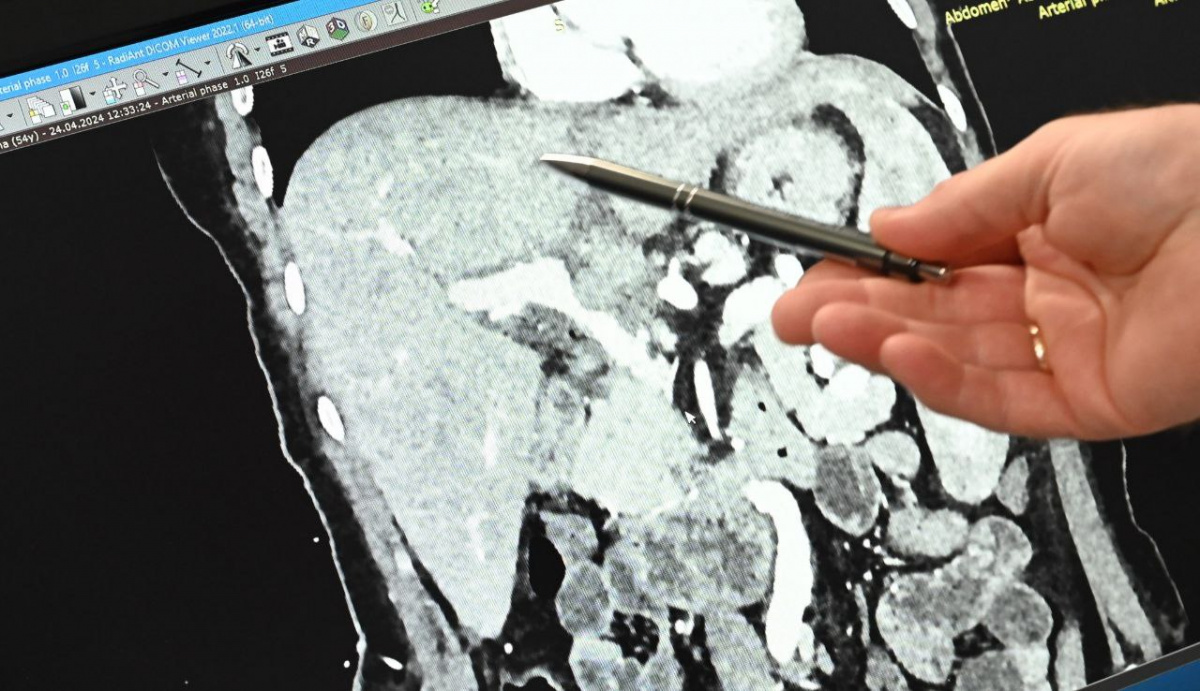

Фото: Людмила Ковалева (архив «Южноуральской панорамы»)